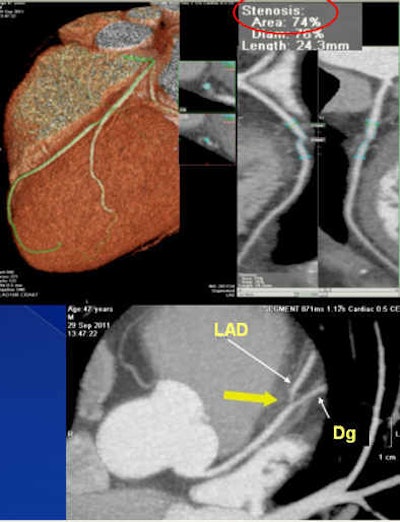

Above and below: In a 47-year-old asymptomatic woman who smoked five to 10 cigarettes per day, CCTA revealed a 74% stenosis (noncalcified plaque) in the proximal left anterior descending artery, with no other significant stenoses in the coronary vessels. In this case, risk stratification schemes would clearly underestimate the patient's cardiovascular risk, even considering her strong family history of having two first-degree relatives who suffered myocardial infarction before age 50, as genetic burden has not been well-studied in young patients. The effective radiation dose was 1.8 mSv. All images courtesy of Dr. Alberto Hidalgo.